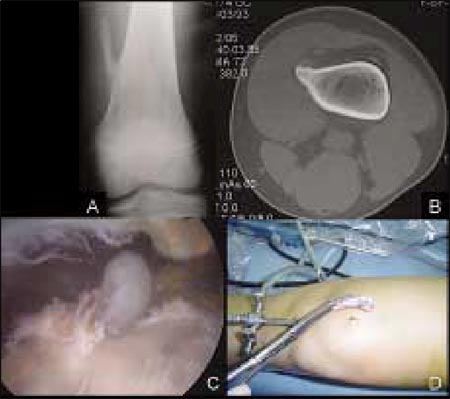

Caso1: Paciente de sexo masculino de 12 años de edad con un osteocondroma de fémur distal izquierdo. A: Radiografía de frente en la cual se observa un osteocondroma pediculado en la cara interna del fémur. B: Corte axial de la Tomografía Computada en la cual se observa continuidad entre la medular y la cortical del hueso normal con la exostosis. C: Visión artroscópica del osteocondroma luego del debridamiento capsular y de partes blandas. D: Resección del tumor por el portal suprapatelar interno.